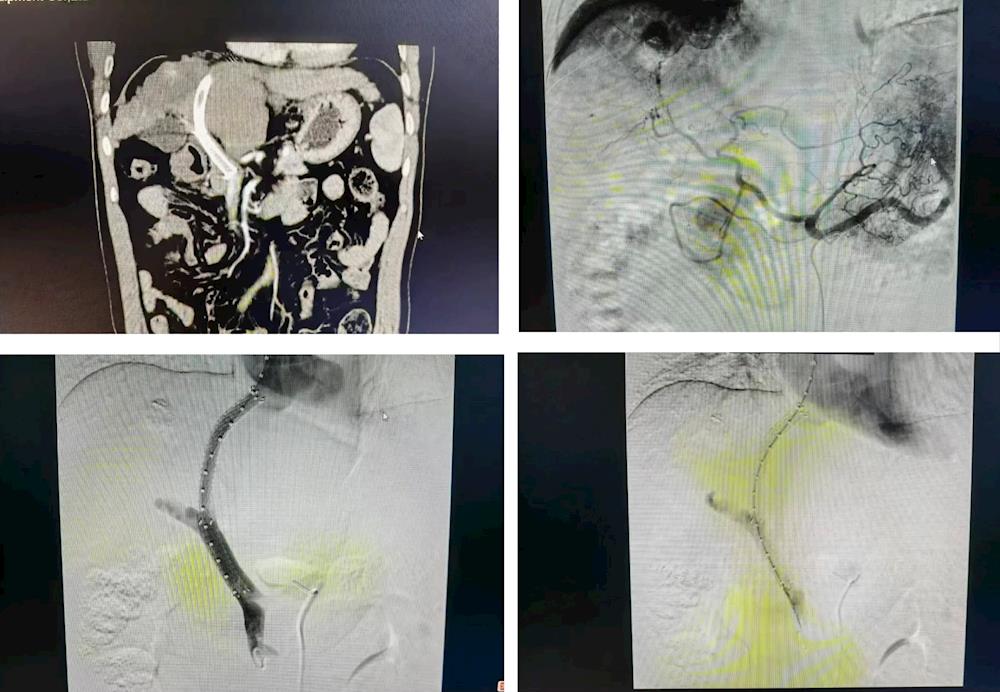

唐大哥到肿瘤科住院后,听说可行介入治疗控制本病出血,抱着“死马当作活马医”的想法,唐大哥与家属商量了一番,决定试一试。2024年2月,肿瘤科欧阳天忠副主任医师手术团队为唐大哥在DSA下行经颈静脉行门腔静分流术,术后患者恢复良好。

术中